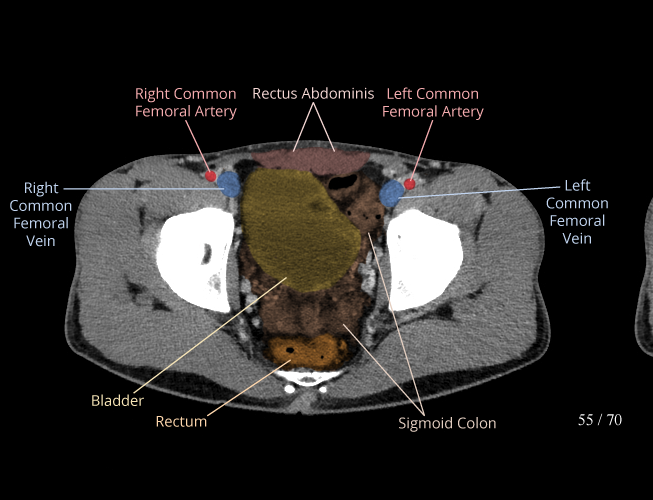

Pelvis

Covers pelvic MRI anatomy.